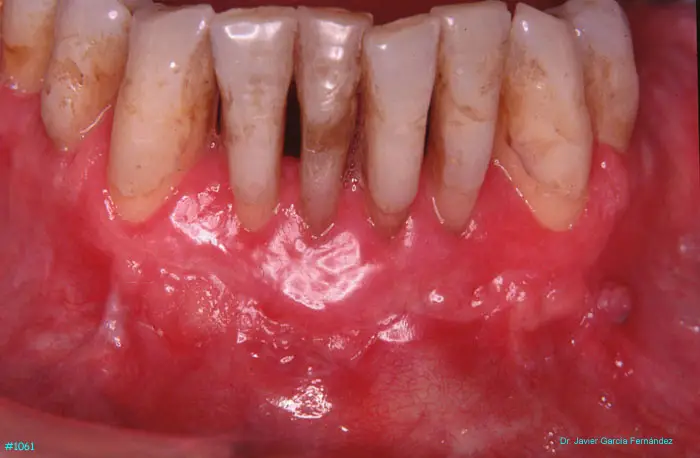

Atlas of Surgical Techniques in Periodontics. Chapter III. Atlas de Técnicas Quirúrgicas en Periodoncia